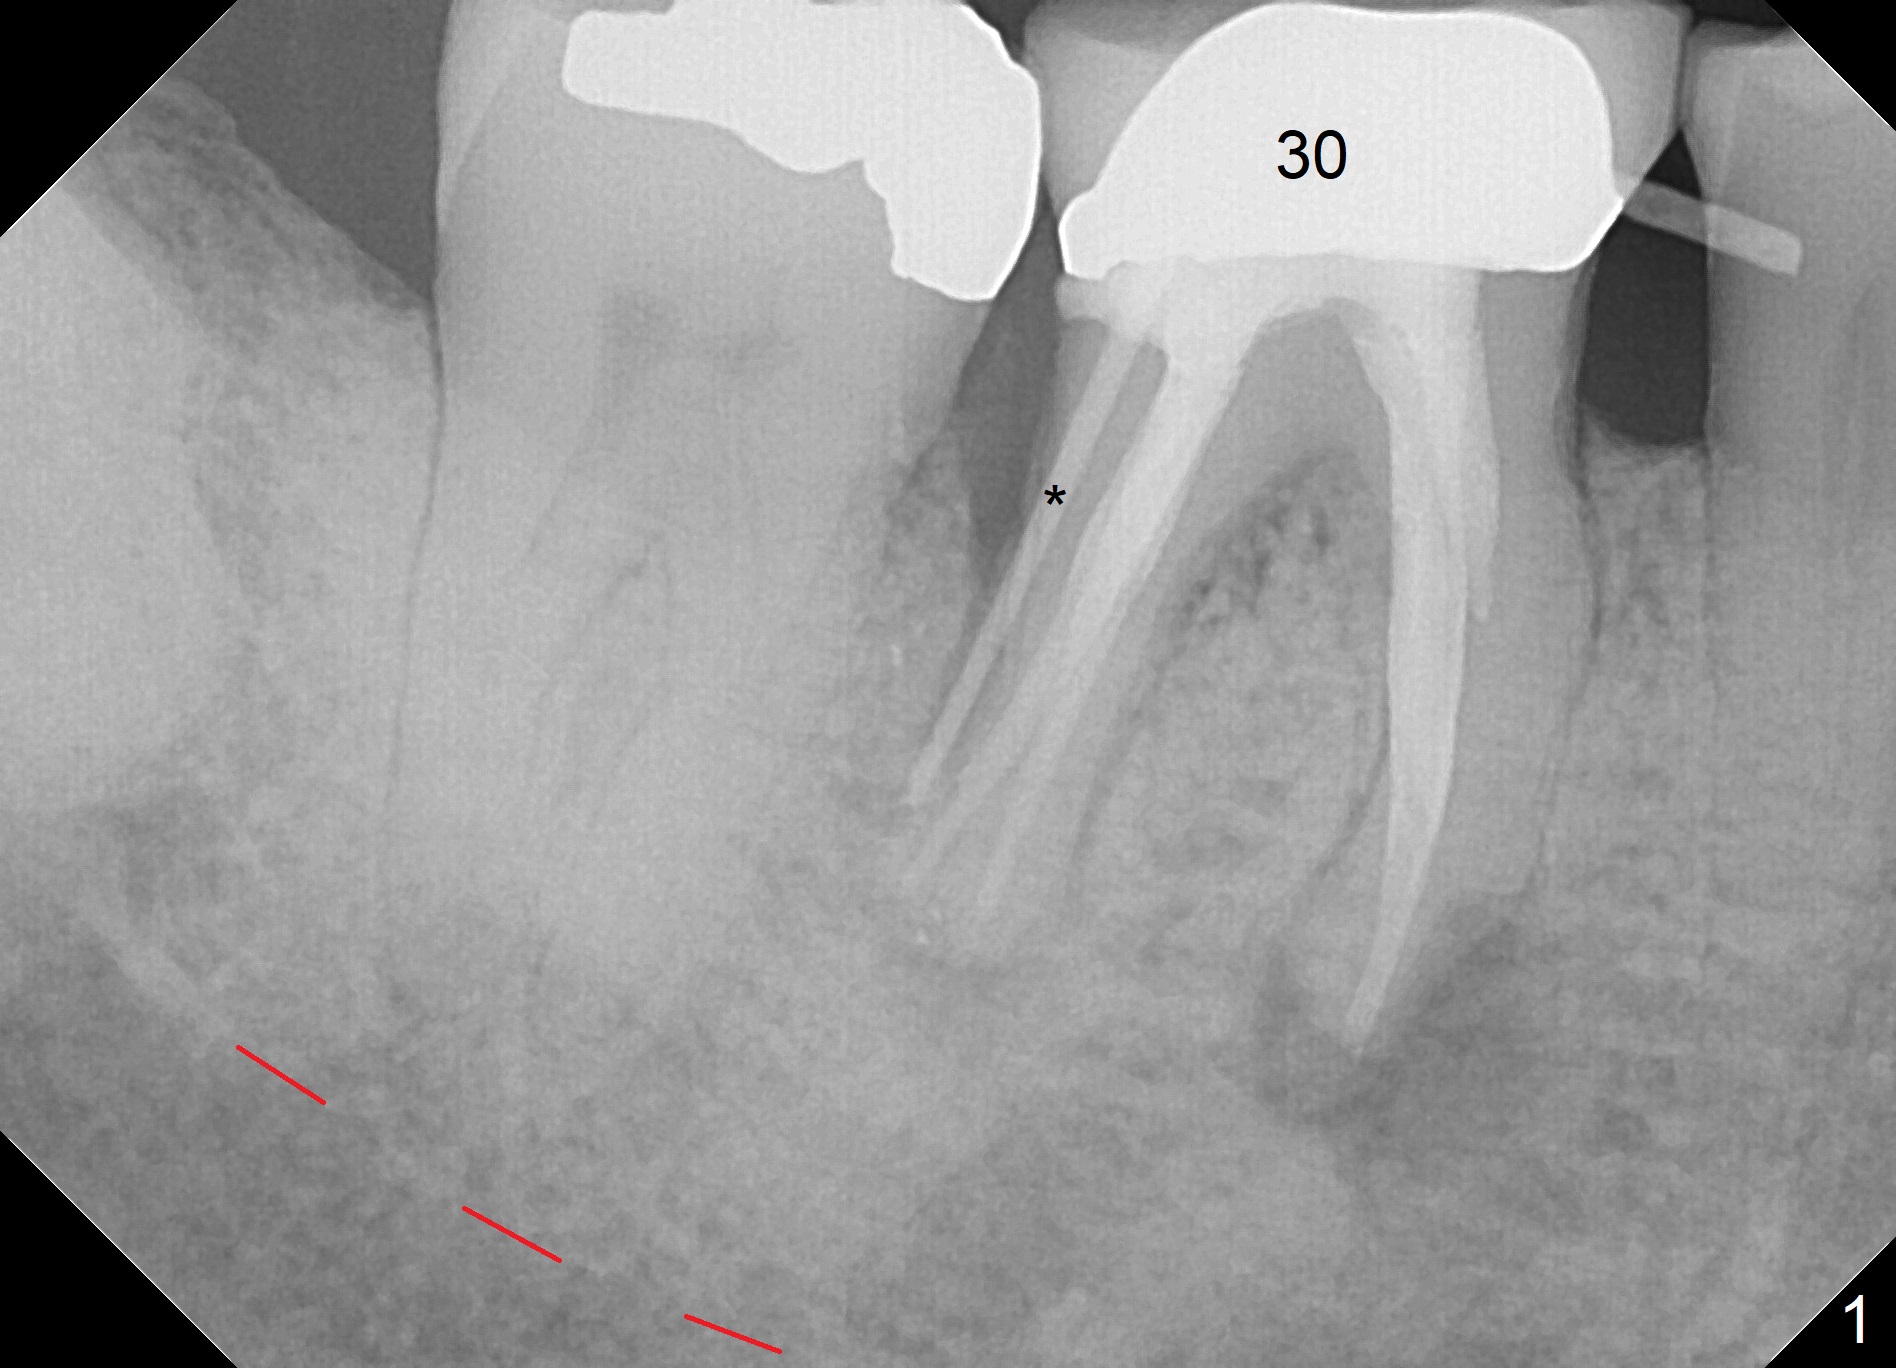

A 79-year-old woman with osteoporosis has pain and buccal swelling 9 years post RCT at #30 (Fig.1 (* gutta percha inserted in fistula)). It appears that the tooth should be replaced by a long implant with better surface treatment for osteointegration (Fig.2). Let the implant heal more than 4 months with progressive loading. Take preop photos to show the buccal infection. For the best trajectory, take PA immediately after 2 mm drill and watch for the deviation of the osteotomy. Place Osteogen plug in the apical portion of the sockets and allograft in the coronal half. Start osteotomy as lingual as possible. The patient is nervous. Comfort her.